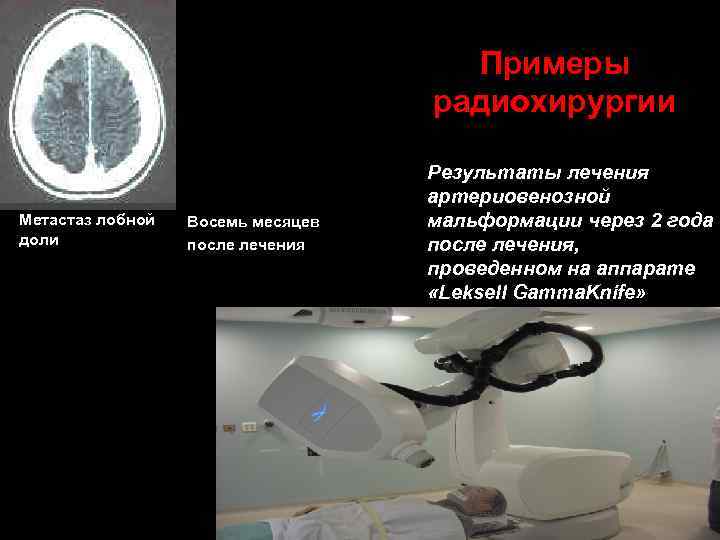

Примеры радиохирургии Метастаз лобной доли Восемь месяцев после лечения Результаты лечения артериовенозной мальформации через 2 года после лечения, проведенном на аппарате «Leksell Gamma. Knife»